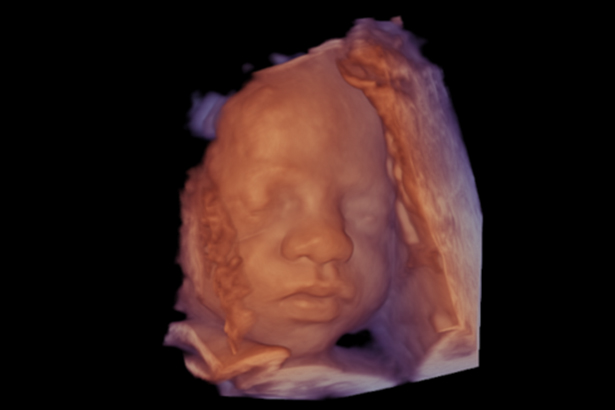

帶來逼真的、高質量和高清晰度的 3D 渲染成像,從早孕期開始即可在深度和細節方面帶來強烈的視覺感受。